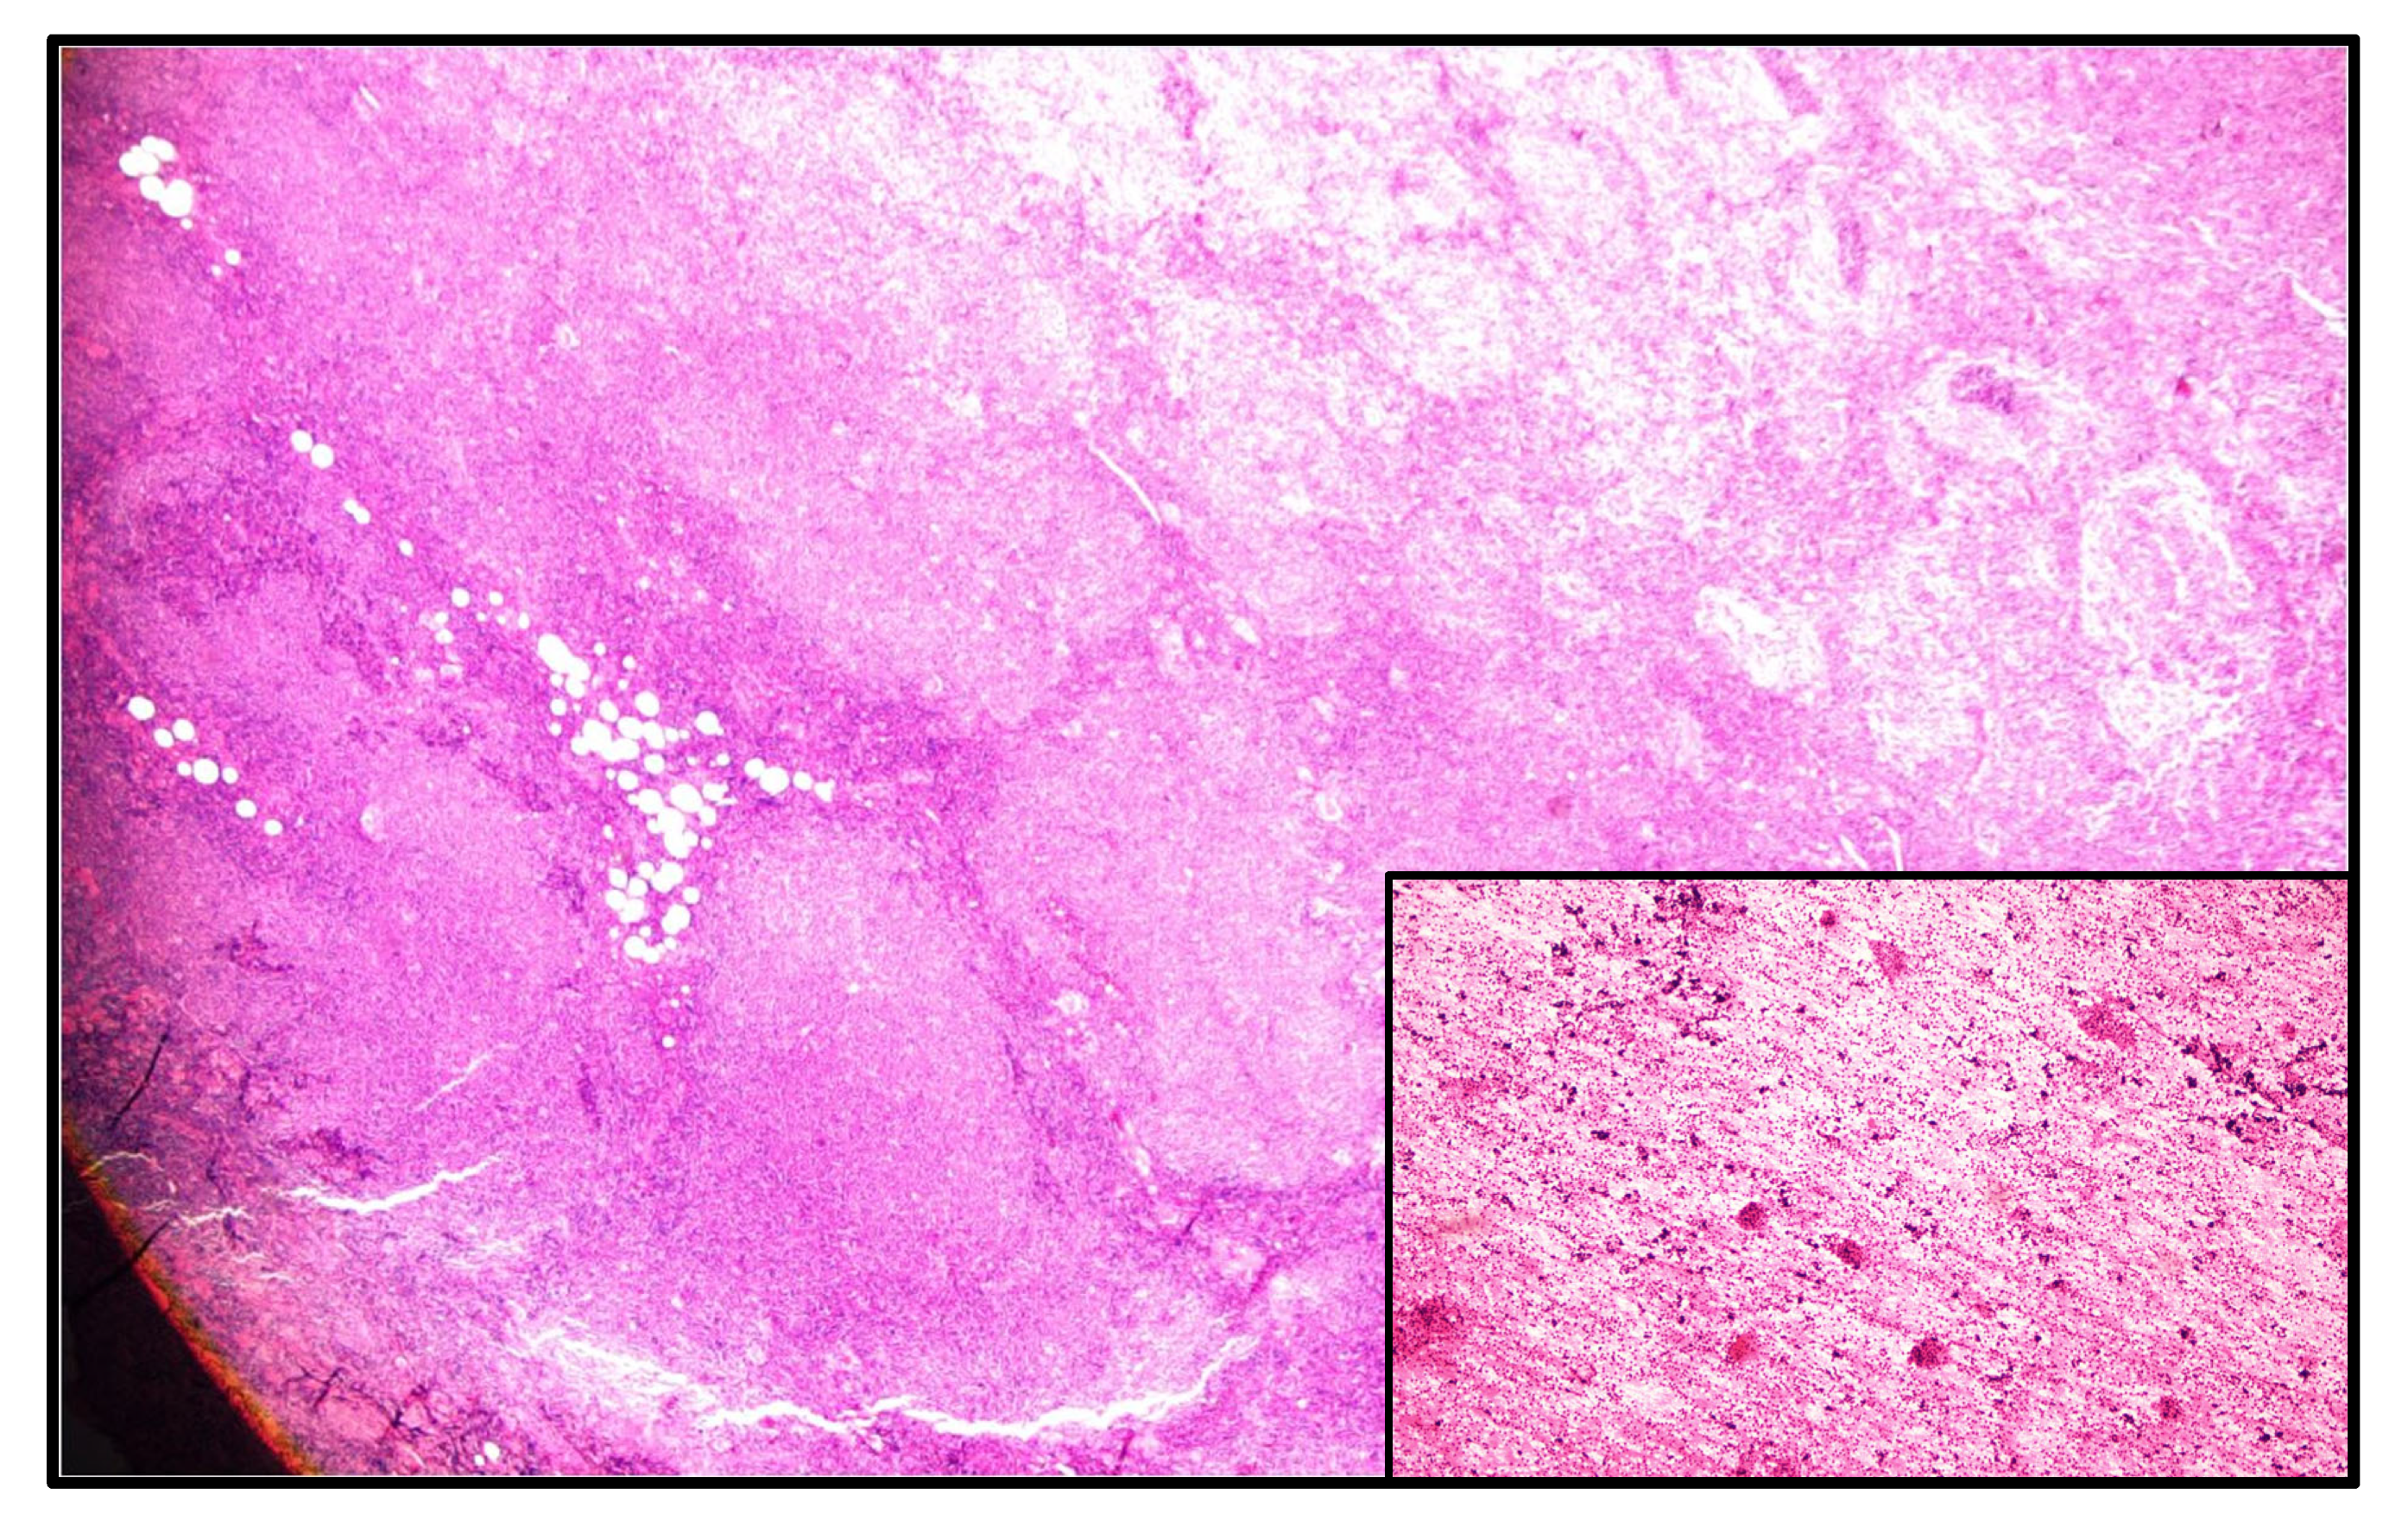

| Current case | 64 | M | Right parotid | WT | Follicular lymphoma/grade 1–2 |